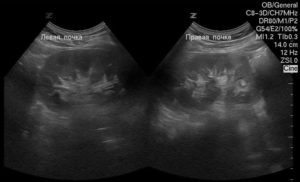

Например, при помощи ультразвукового исследования можно выявить уплотнение почек.

Структурные аномалии этих органов, такие как уплотнение почек, выявляются на УЗИ

Уплотнение — это естественная реакция на воспаление. Уплотнение проявляется в ходе ультразвуковой диагностики, как зона с повышенной эхогенностью, что отличается от волновых характеристик других участков почки.

Также УЗИ устанавливает площадь, локализацию, степень неоднородности тканей и контуры уплотнения, а также другие возможные деформационные изменения.

Как выглядит уплотнение в почках на УЗИ

Изменение эхогенности ЧЛС указывает на их уплотнение. Если стенки собирательной системы утолщаются, интенсивность отражения ультразвуковой волны от их поверхности увеличивается. Во время обследования УЗИ-специалист обязательно заметит:

- изменение размера органа;

- неровность краев;

- неоднородность тканей ЧЛС;

- уплотнение лоханки;

- деформацию чашечек.

Почка покрыта паренхиматозной тканью, которая обладает невысокой эхогенностью. Но при опухолях или воспалении эхогенность увеличивается в разы.

Заключение УЗИ-специалиста нельзя считать диагнозом. Уплотнение ЧЛС – признак патологических изменений в почке, которые вызываются множеством причин.